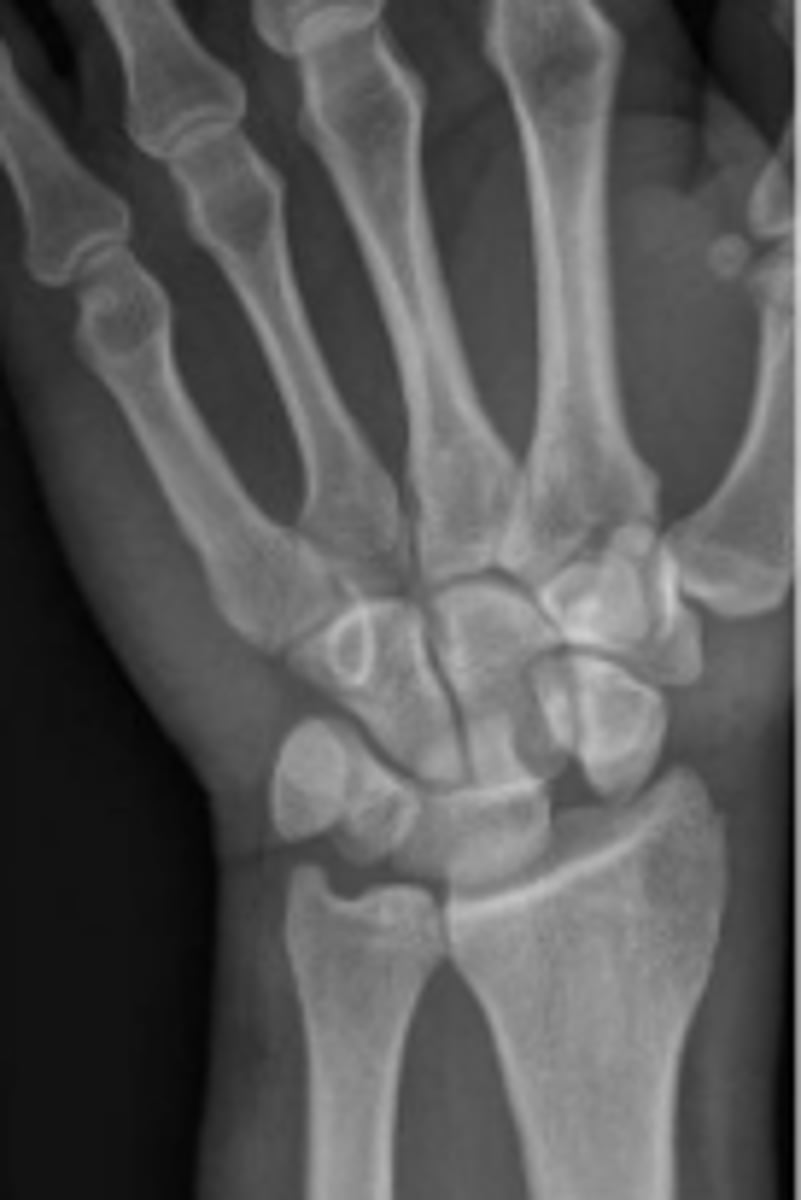

Medial oblique of the right wrist

What is the name of the radiographic view?

Right trapezium

What is outlined?

Right triquetrum

Right pisiform

What is the arow pointing to?

DRUJ

What is the arrow pointing to?

< and equal to 2mm

What is the normal measurement of this space?

Right trapezoid

Right capitate